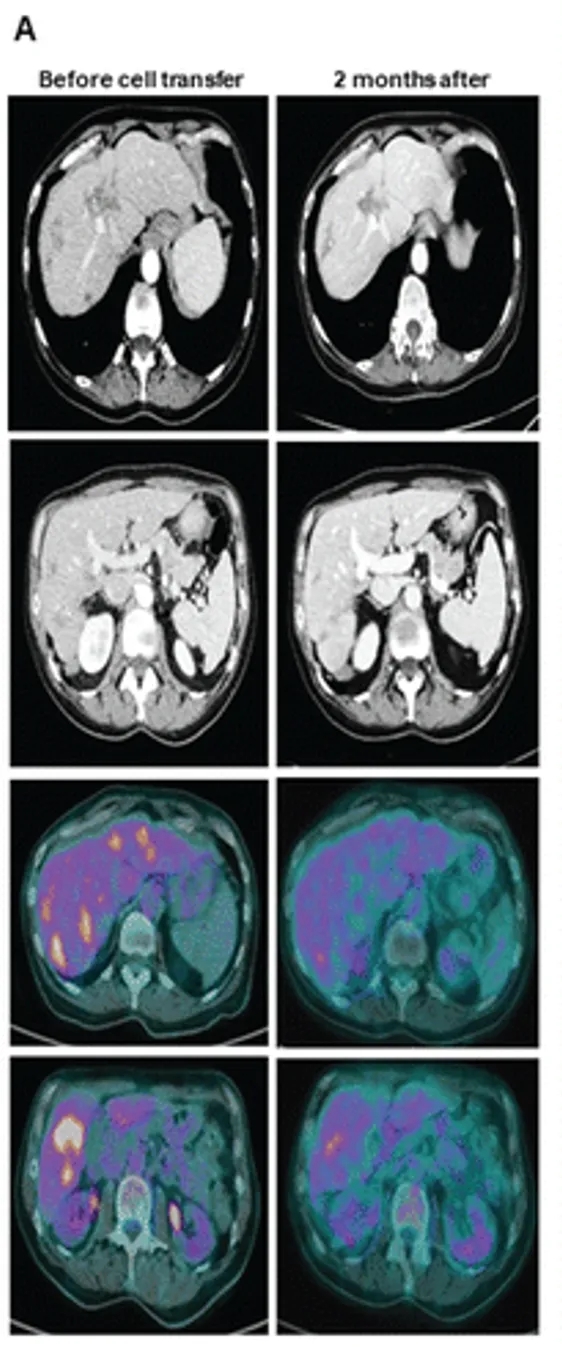

值得一提的是,其中1例(6号患者)的疗效表现尤为亮眼——该患者确诊为KRAS2号外显子野生型结直肠癌,且仅存在肝转移病灶,此前接受包括抗EGFR治疗在内的多种方案均无应答;接受NK细胞治疗后,成功达到部分缓解(PR),FDG-PET扫描进一步证实,其大部分肝转移灶的代谢活性显著降低(详见下图)。

▼该6号患者在接受NK细胞治疗前2个月(左图)、治疗后(右图)的CT及PET对比

▲图源“Oncoimmunology”,版权归原作者所有,如无意中侵犯了知识产权,请联系我们删除